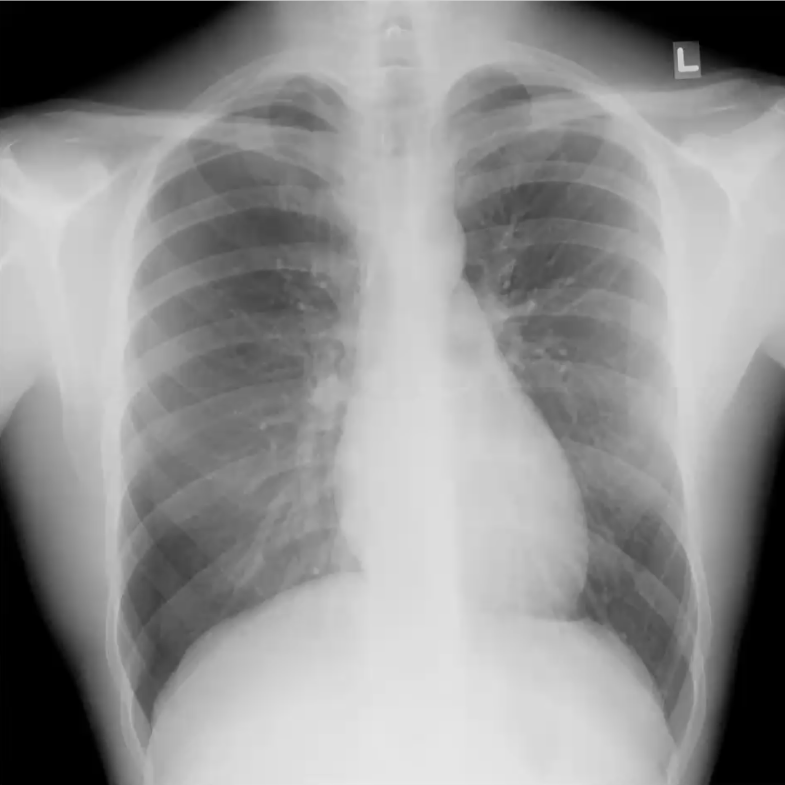

What’s your diagnosis?

Right middle lobe pneumonia because loss of right heart border (silouhette sign)